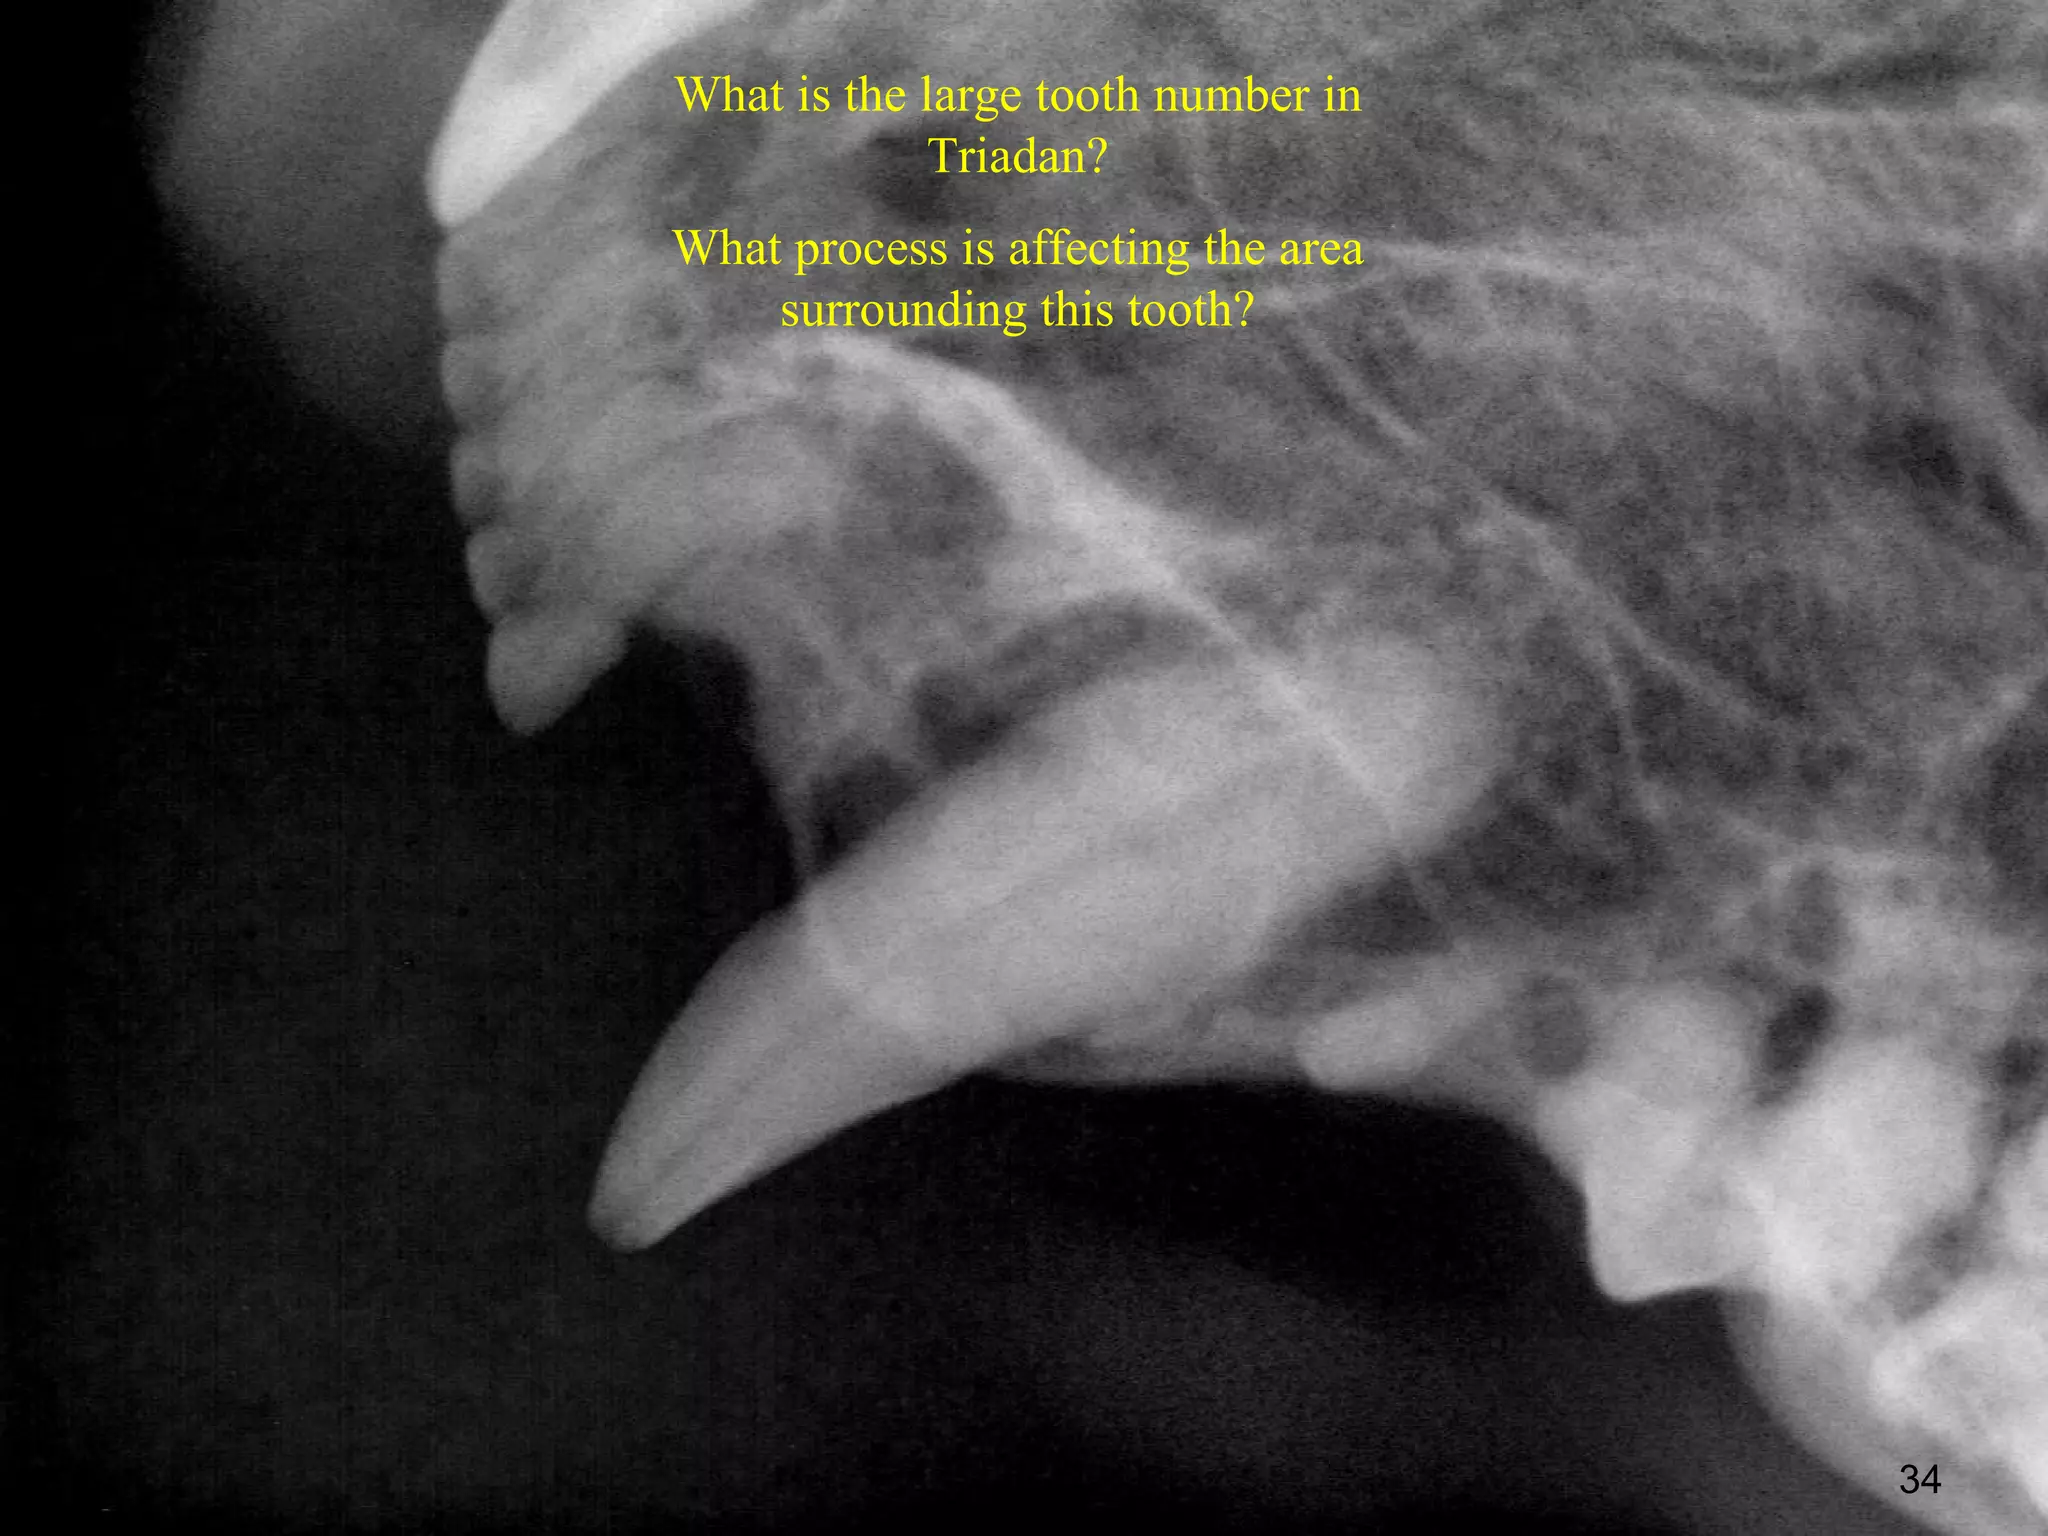

What is the large tooth number in

Triadan?

What process is affecting the area

surrounding this tooth?

34

What is thelarge tooth number in Triadan? What process is affecting the area surrounding this tooth? 34